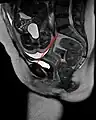

The pelvic inlet (shown in red)

The pelvic inlet or superior aperture of the pelvis is a planar surface which defines the boundary between the pelvic cavity and the abdominal cavity (or, according to some authors, between two parts of the pelvic cavity, called lesser pelvis and greater pelvis). It is a major target of measurements of pelvimetry.

Its position and orientation relative to the skeleton of the pelvis is anatomically defined by its edge, the pelvic brim. The pelvic brim is an approximately apple-shaped line passing through the prominence of the sacrum, the arcuate and pectineal lines, and the upper margin of the pubic symphysis.